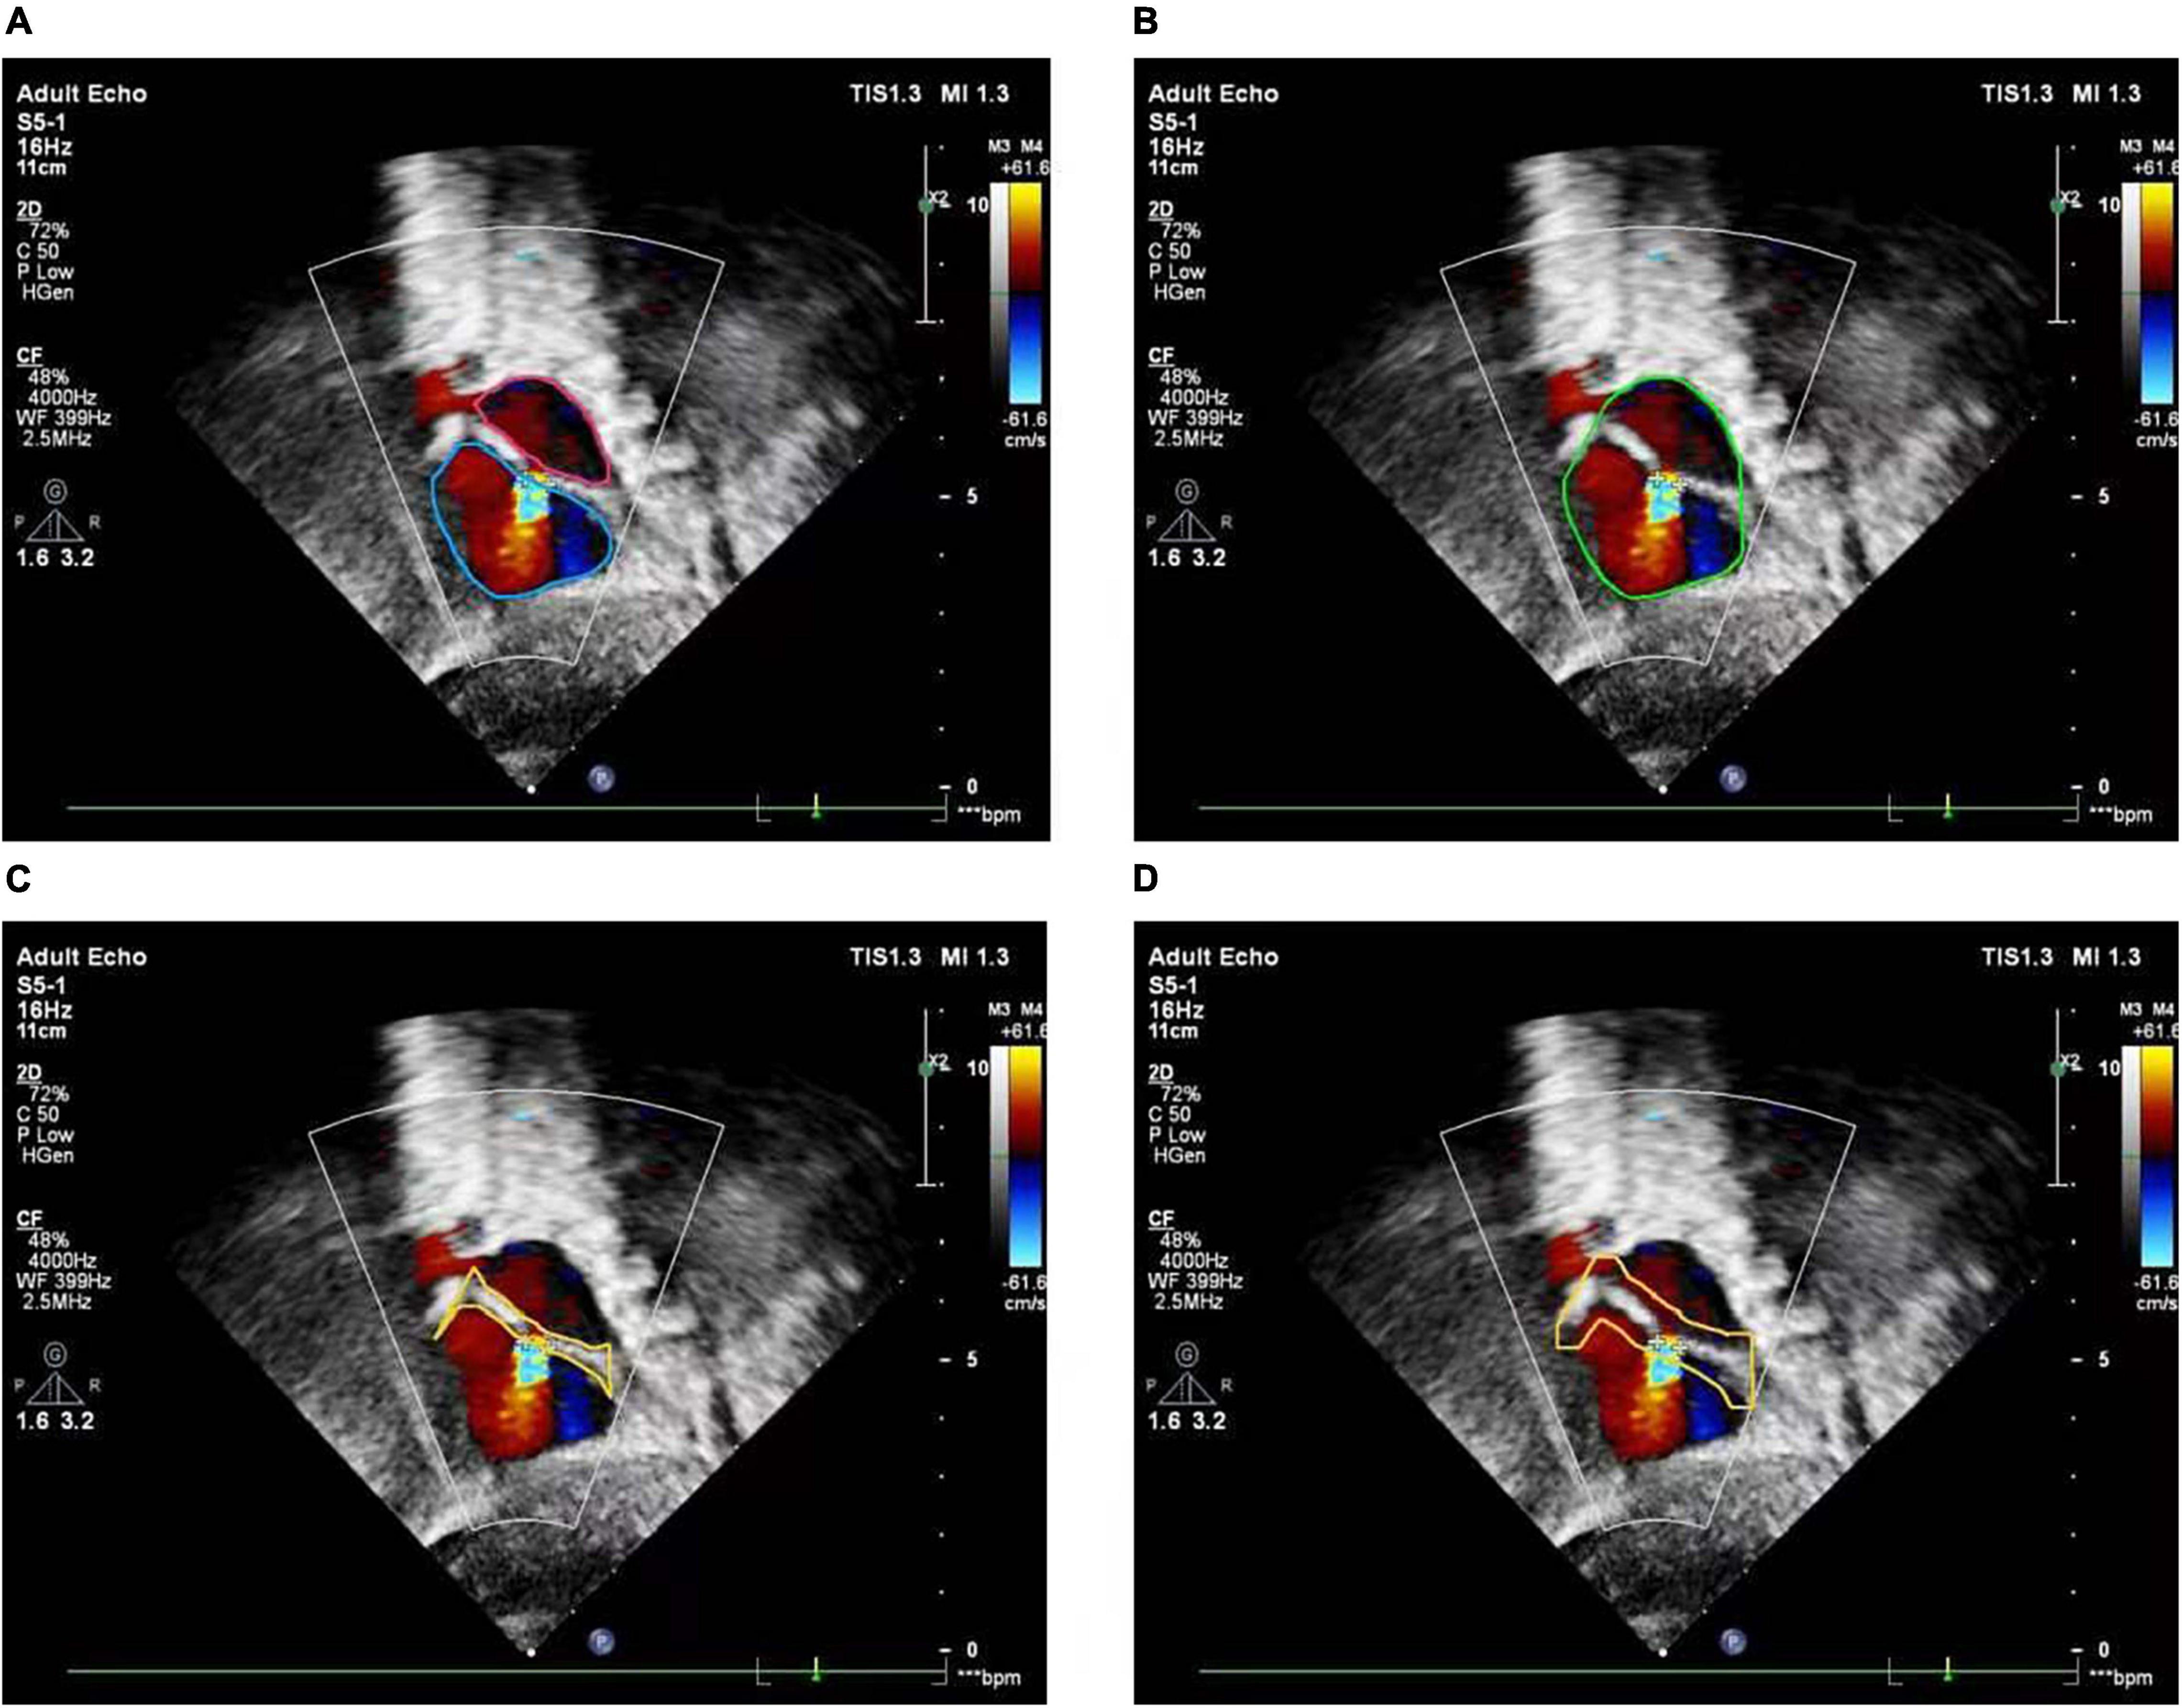

The basic rule of ASD diagnosis is that ASD occurs in the septum area between LA and RA. Theoretically, the ASD candidates detected by the FCOS detector may appear in any area of the image. Therefore, detection refinement is necessary to filtered out false positives detected. Based on the outputs of the cardiac anatomy segmentation, the septum area can be extracted through deterministic spatial analysis. More specifically, we first need to find the smallest convex hull of LA and RA, and then the difference between the convex hull and the area of LA and RA is the septum area. As shown in Figure 5, considering the decision margin, morphological dilation techniques can be used to expand the septum area. Finally, ASD candidates detected outside the septum area are regarded as false positives and filtered, as shown in Figure 6.

Figure 5. Atrial septal region extraction. (A) Segmented left and right atria, (B) convex hull embracing segmented left and right atria, (C) region differences between (A) and (B), (D) morphologically dilated atrial septum.

Figure 6. Atrial septal defect detection refinement. (A) Input image with a target view, (B) detected ASD candidates, (C) segmentation result of cardiac anatomy, (D) extraction of atrial septal region based on (C), (E) final refined result of ASD detection.